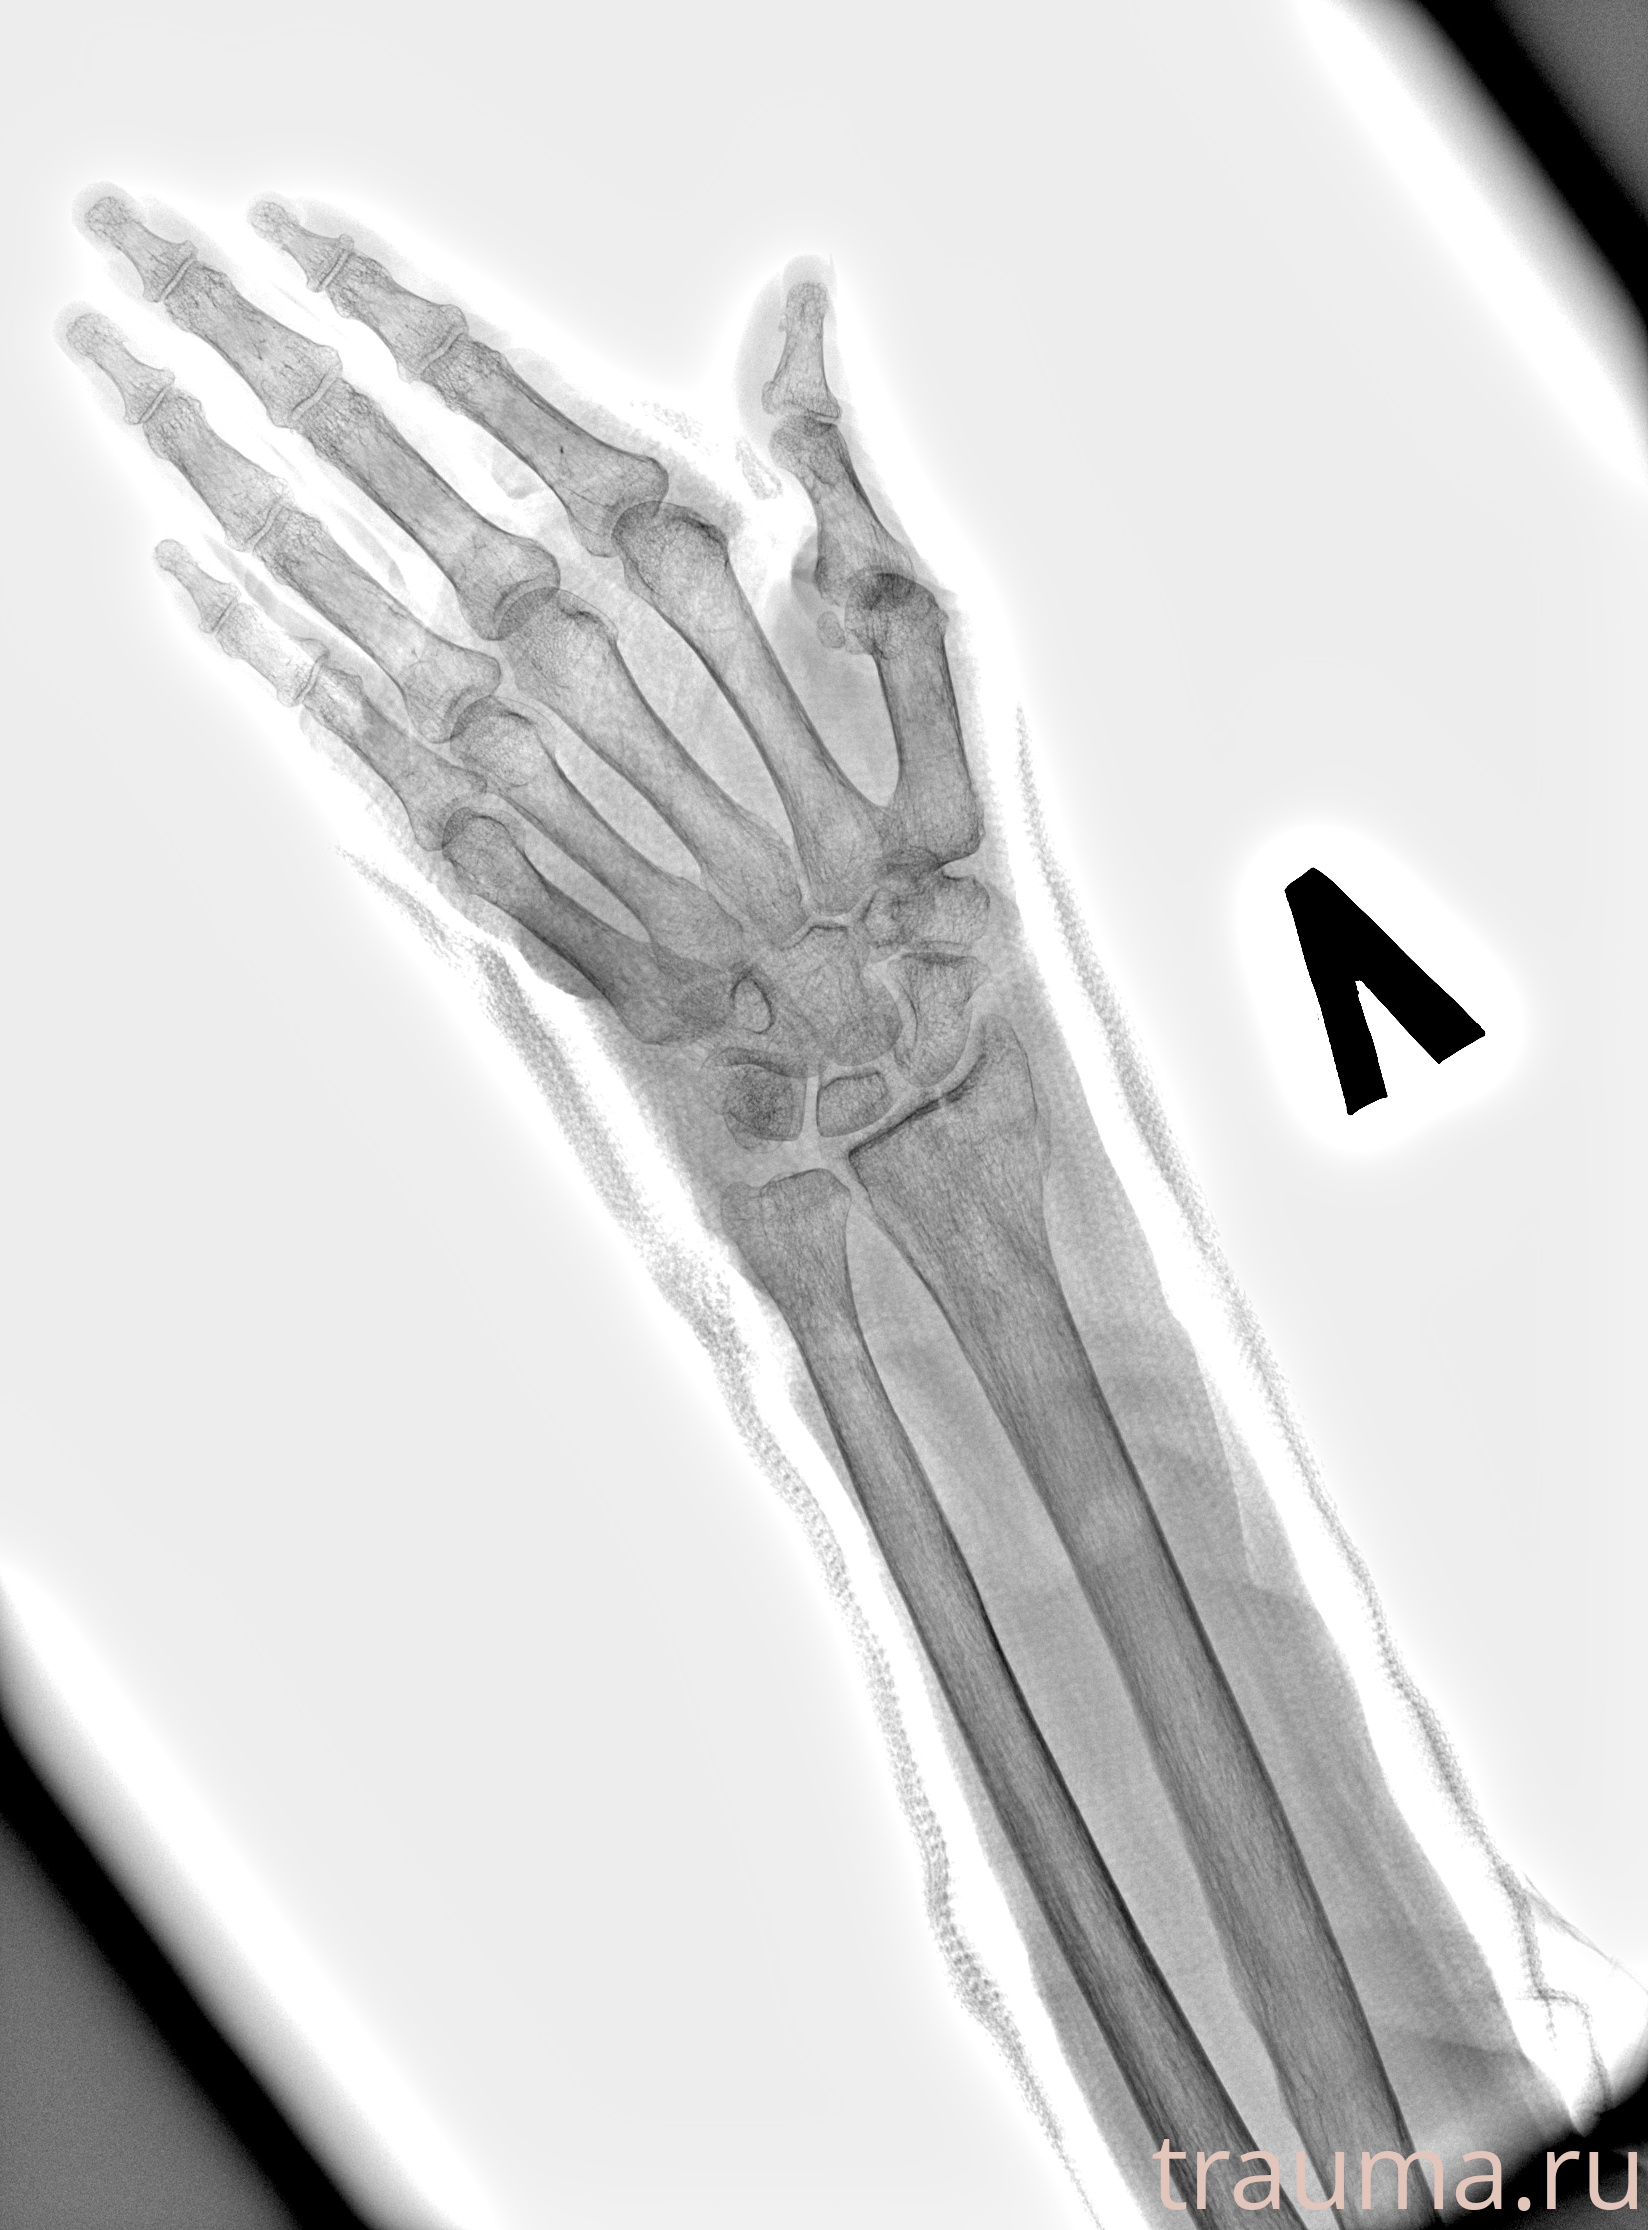

Рентгенограммы

Рентген на дому: по вашему адресу приезжает врач-рентгенолог, травматолог-ортопед с мобильным рентгеновским аппаратом, проводит диагностику травмы или заболевания, делает необходимые рентгенограммы, дает рекомендации по дальнейшему лечению. Получить качественные снимки в домашних условиях возможно благодаря уникальной методике, разработанной МосРентген Центром для института  Склифосовского